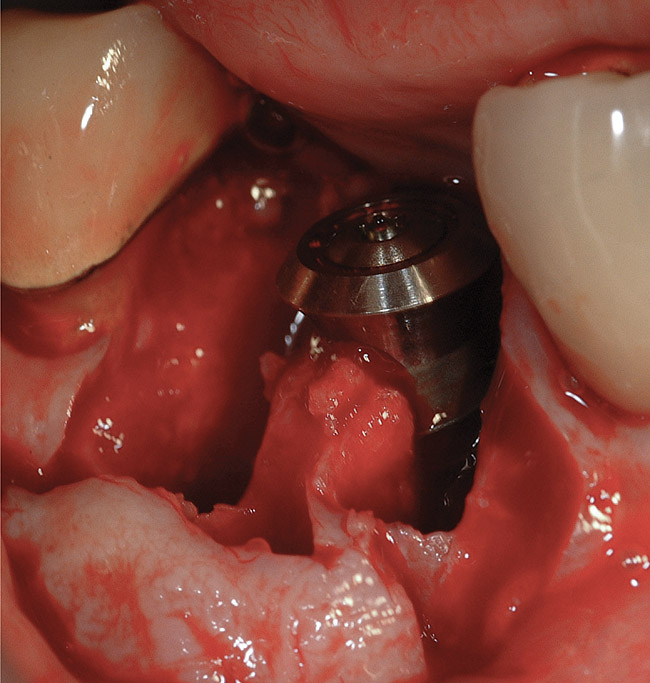

Figure 8  A straight-walled implant with a 4.8-mm diameter and a 6.5-mm restorative platform diameter has been placed in the interradicular bone following tooth sectioning and removal. Primary stability has been attained.

Figure 8

If the most crestal aspect of the interradicular bone is at least 3-mm-wide mesio-distally: A 2.2-mm-wide guide bur is drilled to the appropriate length, a guide pin is inserted, and a radiograph is taken (Figure 7). If necessary, the initial osteotomy is extended apically. A tapered osteotome is inserted into the osteotomy and moved mesio-distally and bucco-lingually to expand the osteotomy site. A 2.8-mm bur is used to prepare the osteotomy to depth, and a 2.8-mm-wide tapered osteotome is inserted in the osteotomy and once again utilized in mesio-distal and bucco-lingual directions to expand the osteotomy site. If the mesial and distal aspects of the interradicular bone are still intact at this point, a 3.5-mm bur is utilized to prepare the osteotomy to depth. A 3.5-mm-wide osteotome is inserted into the osteotomy and utilized in the manner already described. A decision is made as to whether to place a tapered implant with a 4.1-mm-wide base and a 6.5-mm-wide neck, or to use a 4.8-mm-wide bur and prepare the osteotomy to depth, in anticipation of placement of an implant with a 4.8-mm-wide parallel wall body and a 6.5-mm-wide platform. The chosen implant is inserted into the osteotomy (Figure 8), appropriate regenerative materials are placed, and the flaps are sutured. Following maturation of the regenerating hard tissues, the implant is ready for restoration (Figure 9). A radiograph taken 54 months after implant restoration demonstrates stability of the peri-implant crestal bone (Figure 10).